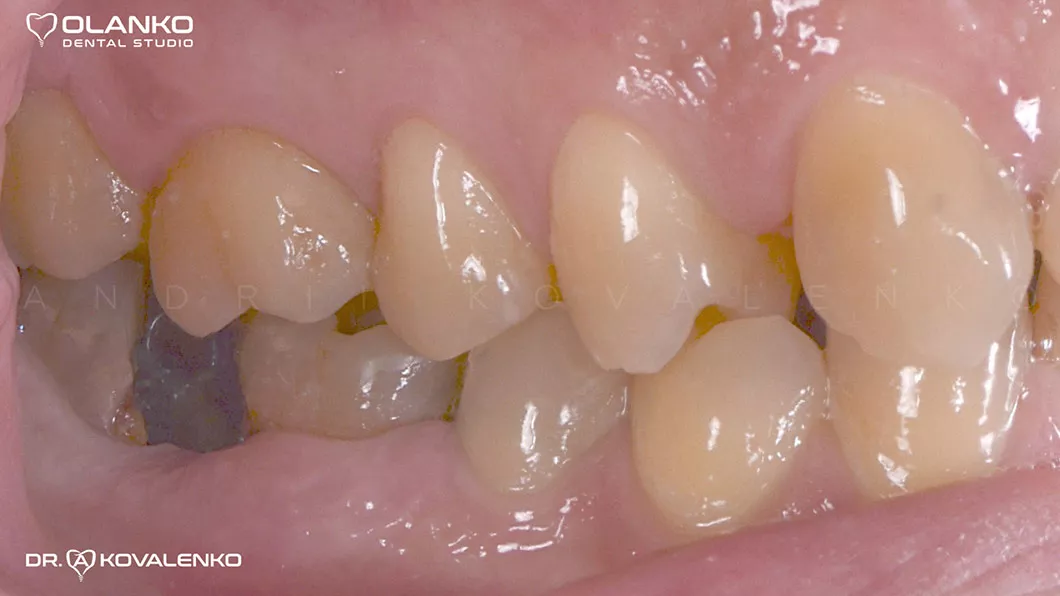

Вид через 4 месяца после удаления

Вид перед установкой коронок через 3 месяца после установки имплантатов

Лечение: удаление 2-х не подлежащих лечению зубов. Установка двух  имплантатов, с последующей установкой цельнокерамических коронок на индивидуальных абатментах.